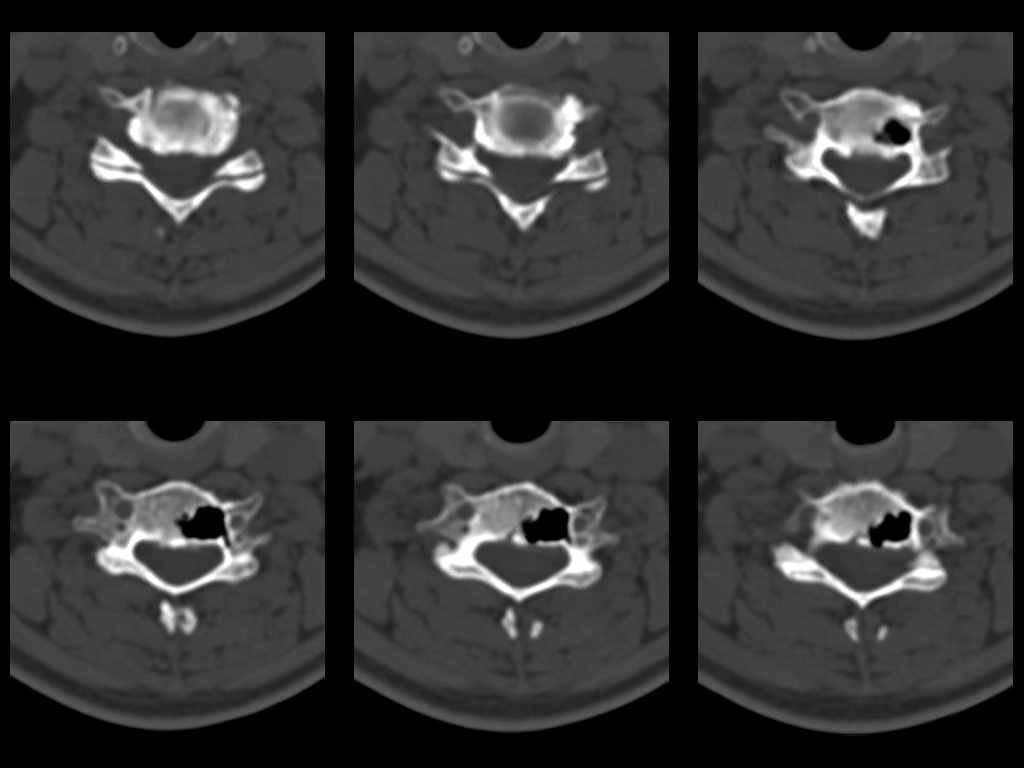

У женщины 49 лет, при рентгенографии шейного отдела в теле С6 выявлен участок деструкции.Часть N1 Больная находилась в неврологическом отделении с диагнозом энцефалопатия. Была проведена КТ тела С6, 26.12.2002 выявлен участок деструкции 0,9х1,2 см, плотность участка составляет -1022 ед.Н. аналогичная плотности воздуха в трахее.Возникает вопрос что это? Метастаз, киста,или какой то вредный анаэроб грызет тело позвонка?Через пол года 03.06.2003 произведено повторное исследование. Отмечается отрицательная динамика. Участок деструкции увеличился в размерах, увеличелась площадь разрушения задней поверхности тела С6.

Первые 2 серии снимков это от 2002г, вторые 2 серии от 2003 г. Относительно размеров, сообщю дополнительно все перермерю на томографе.

Размеры за 2002 год 1,2х0,9х1,2 мм

за 2003 1,3х0,9х1,2 мм. Но контур деструкции стал более неровный и внедрение в дужку С6 увеличелось.

Наличие выраженных дистрофических изменений, а также сообщение полости в теле позвонка С6 с полостью межпозвонкового диска в сегменте С5-С6, а также наличие газа в полости межпозвонкового диска С5-С6 спереди, на границе фиброзного кольца и пульпозного ядра (3-й слева срез в нижнем ряду на второй из представленных КТ) делает диагноз остеохондроза, осложненного вакуум-феноменом и прорывом газа в полость тела позвонка с формированием воздушной кисты (пневмкисты) несомненным.